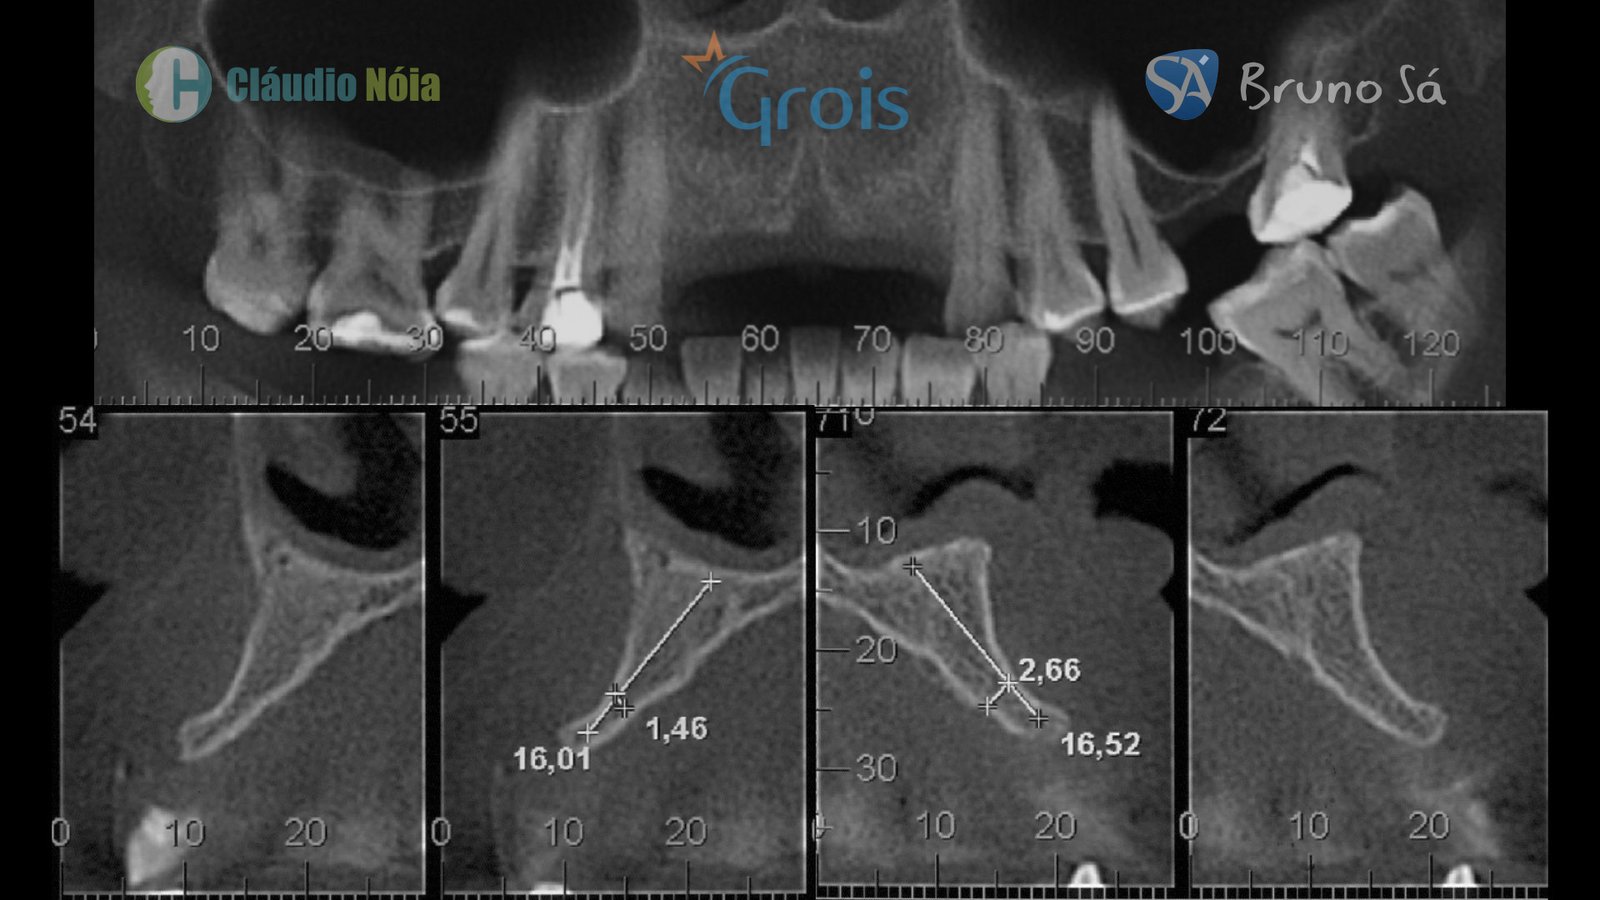

O bom posicionamento dos implantes é pré-requisito fundamental para obtenção de uma reabilitação implantossuportada adequada aos pacientes. No entanto, para se alcançar esse posicionamento tridimensional ideal dos implantes é necessária quantidade e qualidade óssea no leito implantar. Em situações que o remanescente ósseo é insuficiente, torna-se necessário o emprego de técnicas reconstrutivas, e dentre elas estão técnicas como enxerto autógeno em bloco, osteotomias expansivas como a técnica Split Crest, regeneração óssea guiada e técnica Screw Tent Pole.

Paciente apresentou-se a Área de CBMF da Instituição com a pré-maxila edêntula (Figuras 1, 2 e 3) e foi submetido a técnica Screw Tent Pole utilizando os parafusos da linha Orth – Implacil de Bortolli (Figura 3). Do lado direito da pré-maxila foram instalados 3 parafusos que apresentavam roscas em toda superfície, enquanto que do lado esquerdo foram instalados 3 parafusos que não apresentam roscas no terço cervical (Figuras 4, 5, 6, 7 e 8). Biomaterial associado com PRF (Stick Bone) foi adequadamente acomodado na região e recoberto por membranas de PRF (Figuras 9, 10 e 11). Uma sutura livre de tensão foi realizada para finalizar o procedimento cirúrgico (Figuras 12 e 13).